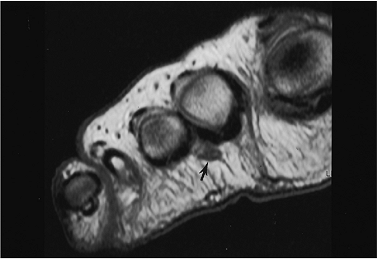

FIGURE 6-66 Axial T1-weighted image demonstrating a Morton’s neuroma (arrow).